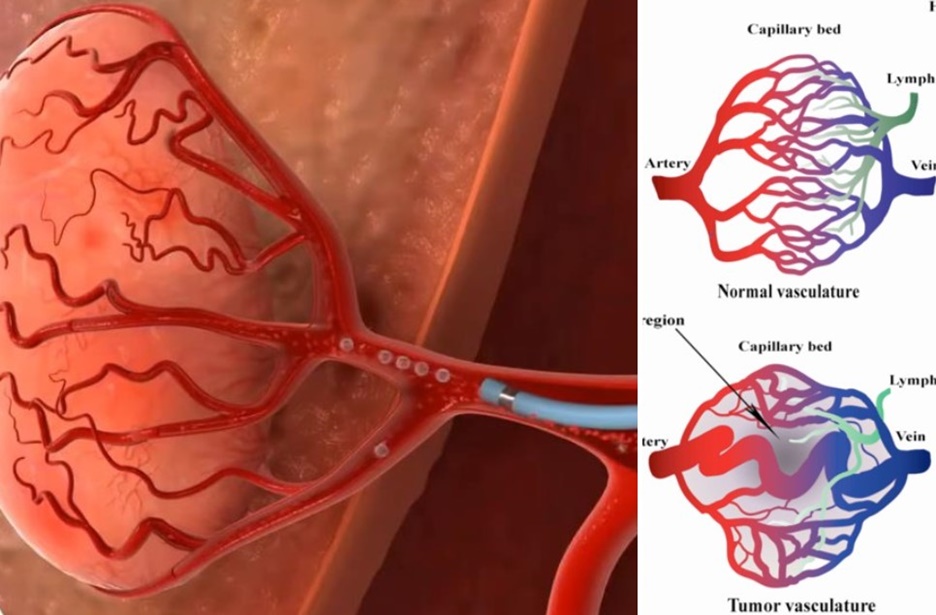

종양 색전술은 종양으로 영양을 공급하는 영양 동맥(Feeding artery)을 '색전'하여 종양세포 성장에 필요한 영양분과 산소 공급을 차단해 괴사를 유도합니다. 최소침습 시술, 종양 색전술 치료를 진행한다면 간종양의 성장을 저해하고 크기 감소시킬 수 있으며, 치료 후에는 활력과 식욕 모두 이전으로 회복될 수 있습니다. *수술적 절제가 어려운 간종양의 경우 '종양 동맥 색전술'을 통해 종양의 성장을 막고 크기를 감소시킬 수 있습니다.

최소침습 시술, 색전술은 특히 제거가 어려운 위치나 수술적 예후가 안 좋은 간종양 치료에 효율적입니다. 정상 간세포와 간종양 세포의 혈관분포 차이 덕분에 색전술은 간세포에 손상을 최소화하면서 '선택적'으로 간종양 세포의 '괴사'를 유도할 수 있습니다.